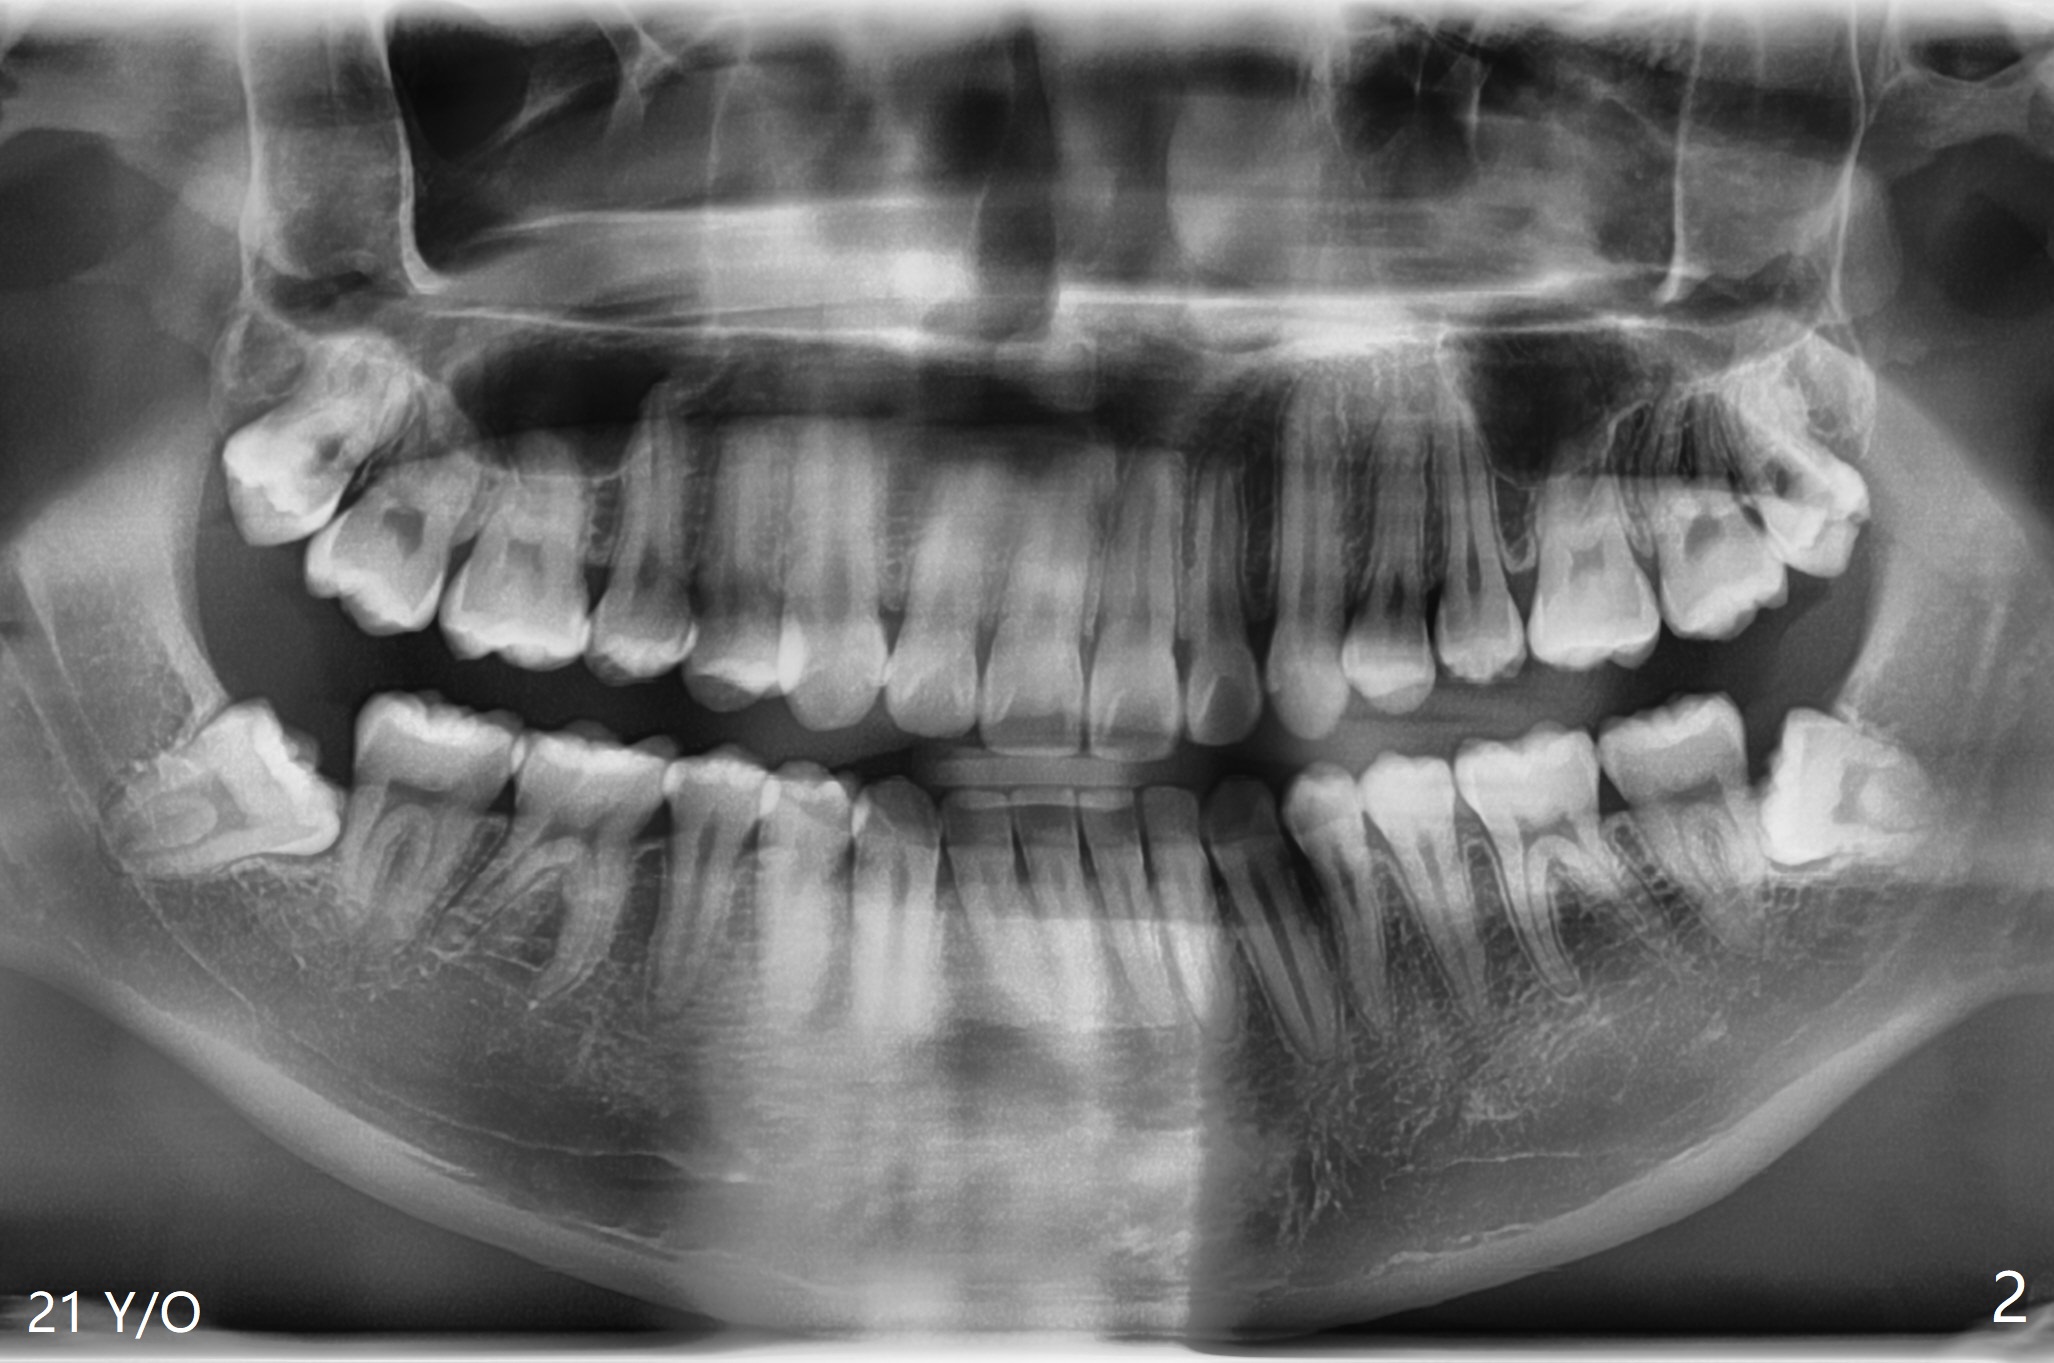

21岁男,大学毕业,即将到外州工作,害怕拔除智齿,要求拔除左下无症状智齿(图一,二)。估计智齿可能位于第二磨牙远中颊侧,